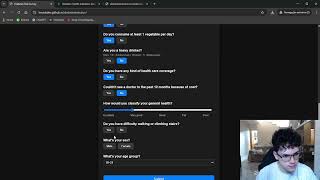

Flask Based App for Entering Human Health Data and Storing them in a Database by Jack Aarts

Flask based application for entering, storing and deleting human health data and plotting graphs of these data by a registered user, which has been logged in.